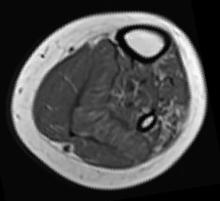

Scan of thigh from an ALS patient. Bone is white. Muscle is grey.

Muscle Atrophy and Childhood ALS Here is scan of an ALS patient’s thigh which shows signs that the muscle has atrophied. The patient was part of an NIH led study which found that a new type of childhood ALS is linked to gene called SPLTC1. Courtesy of NIH/NINDS.

Like many of the other patients, Claudia needed a wheelchair to move around and a surgically implanted tracheostomy tube to help with breathing. Neurological examinations by the team revealed that she and the others had many of the hallmarks of ALS, including severely weakened or paralyzed muscles. In addition, some patients’ muscles showed signs of atrophy when examined under a microscope or with non-invasive scanners.